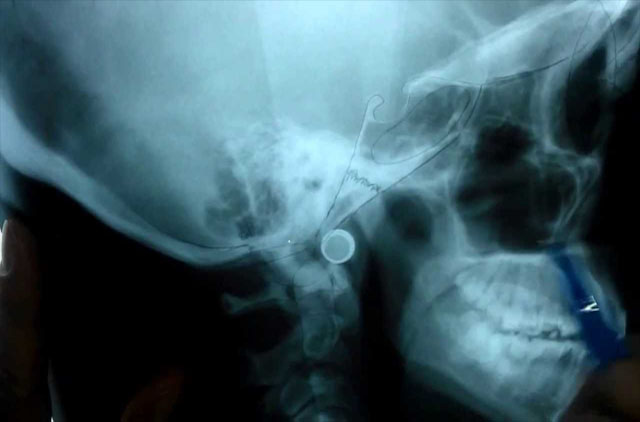

Tomografía 3D (Disponible en sucursal Guelatao y Roma)

La diferencia radical entre la tomografia cone-beam (TCB) y la tomografia computarizada (TC) es la forma de procesar la imagen, es decir la TC es generada a partir de imagenes 2D en la cual se producen aberraciones o distorsiones, sin poder usarla con un poder fidedigno, en cambio la TCB la reconstruccion se hace a través de cortes, sin provocar distorsiones, deja una escala 1:1.

-Trazos Cefalométricos, tomografía volumétrica cone-beam